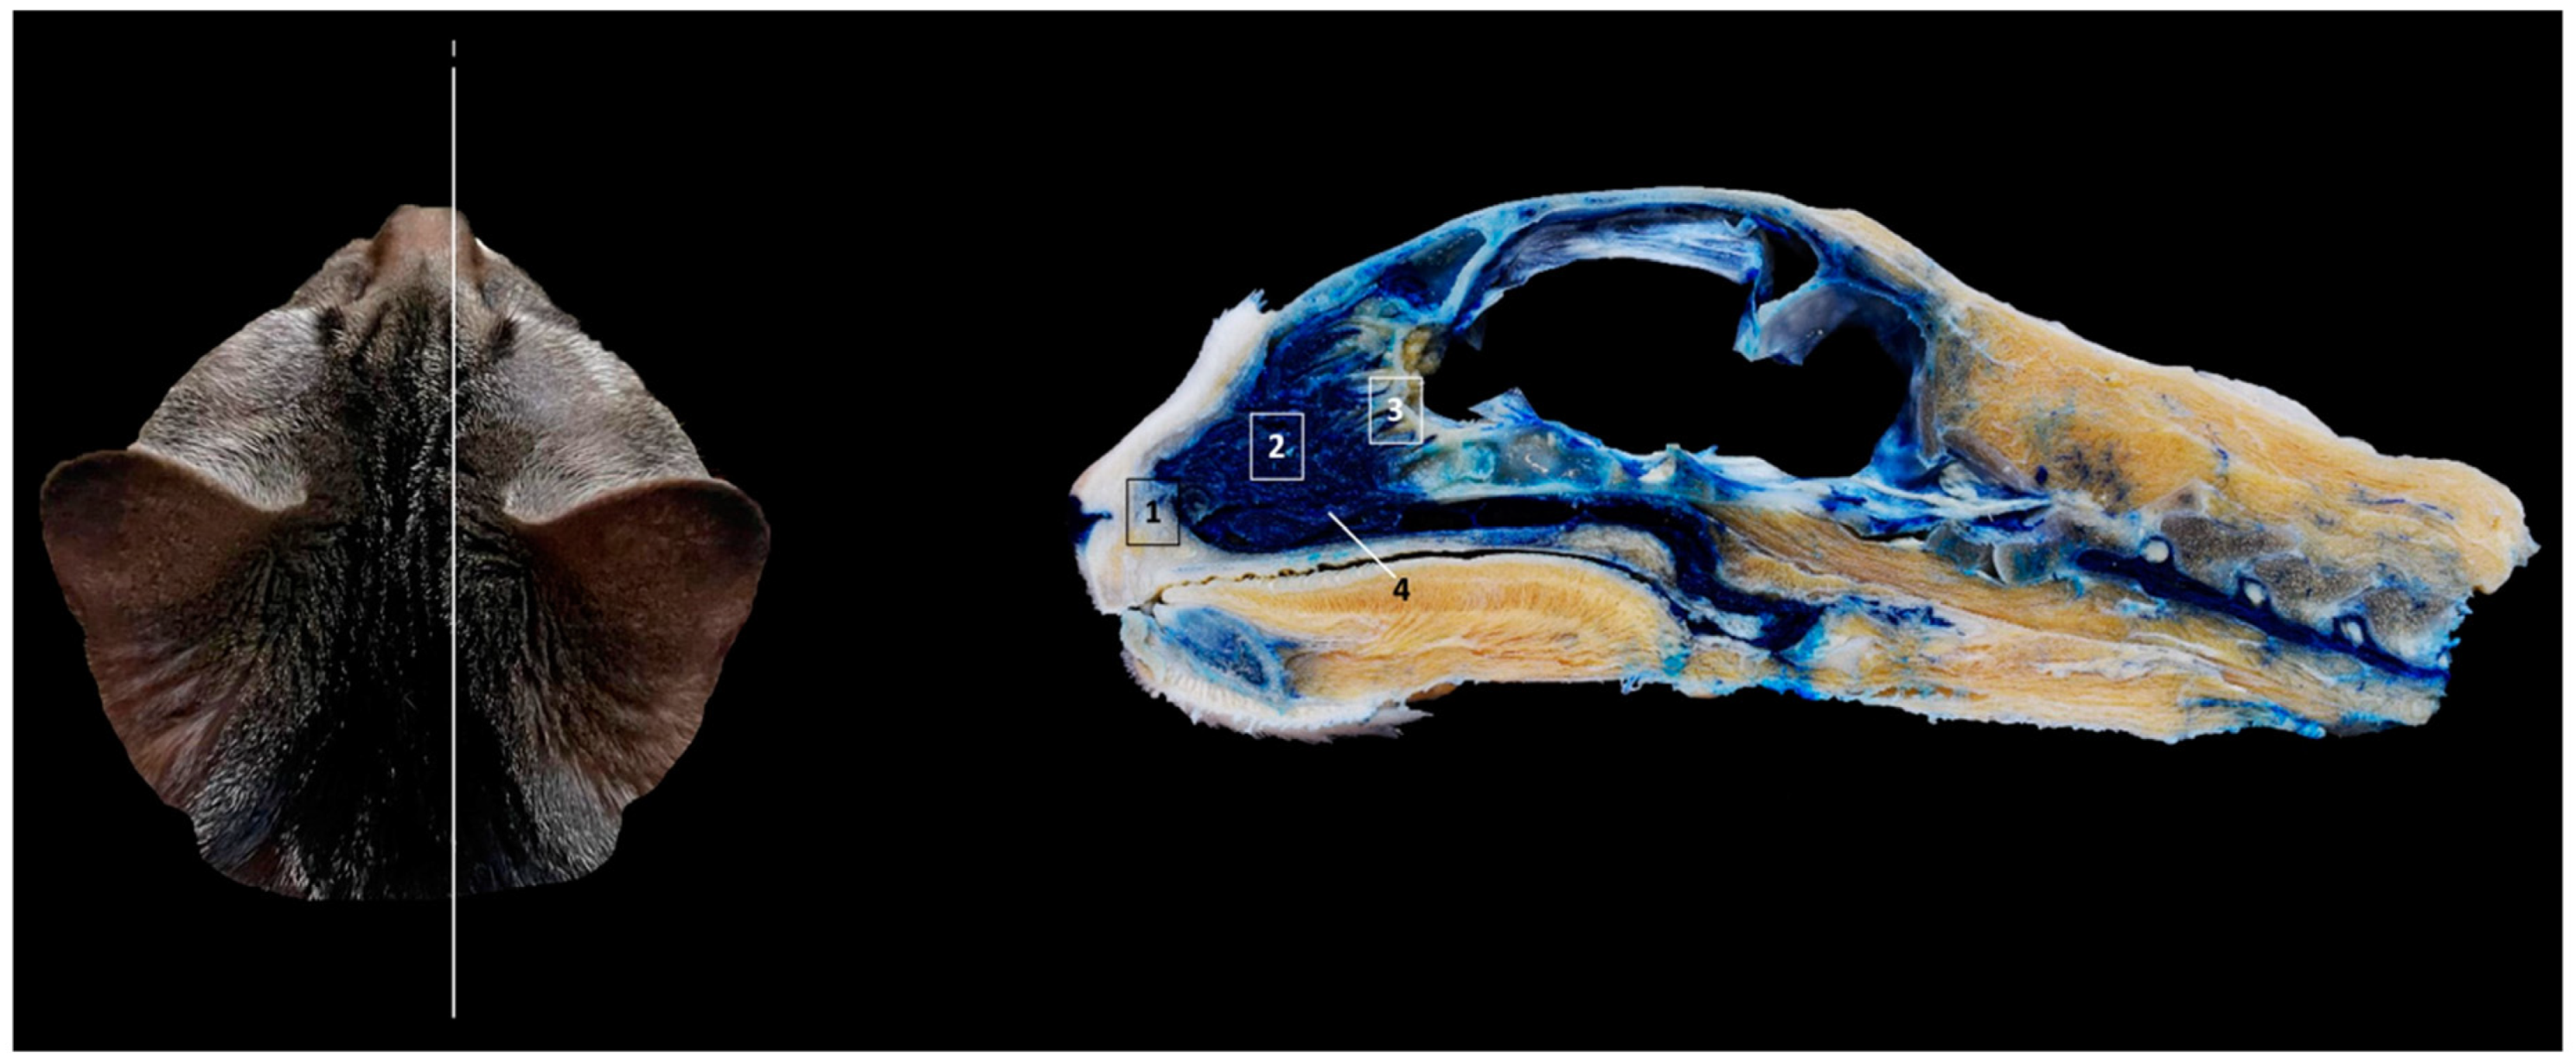

Finally, Figure 18 shows a sagittal section after injection of blue latex to better highlight the vascularization of the respiratory part of the nasal cavity. It is worth noting the extensive blood supply to the respiratory part of the nasal cavity due to the large number of nasal cavernous plexuses that exist at this level and their scarcity in the olfactory part.

Figure 18. Sagittal anatomical section of the cat’s head at the level of the nasal cavity and paranasal sinuses, level I. The venous plexuses have been injected with blue latex via an external jugular vein. The image is oriented so that the rostral part is to the left and the dorsal is at the top. Left lateral view. 1. Nasal vestibule; 2. Respiratory part; 3. Olfactory part; 4. Nasal cavernous plexuses.